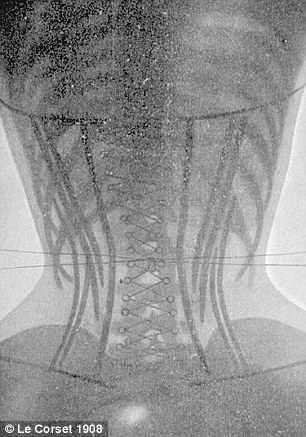

De la coaste si inimi strivite, la spline care isi schimba locul in organism, radiografiile femeilor din Epoca Victoriana arata toate efectele devastatoare ale corsetelor. Totul in numele frumusetii.

Le Corset (n.r. „Corsetul”) este o enciclopedie scrisa de medical francez Ludovis O’Followell la inceputul secolului XX. Imaginile ilustreaza impactul modei asupra sanatatii.

In radiografiile „normale” se pot vedea coaste paralele si organe pozitionate corect. In cele facute unor femei care au purtat corsete, descoperim coaste indoite si organe pur si simplu strivite.

„Corsetele comprima continutul torsului, in special inima si plamanii”, a explicat medicul Natalie Azar.